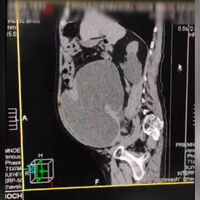

«На фото виден переполненный мочевой пузырь, который занимает большую часть брюшной полости. После постановки уретрального катетера выведено 9 (!) литров мочи», — рассказали медики.